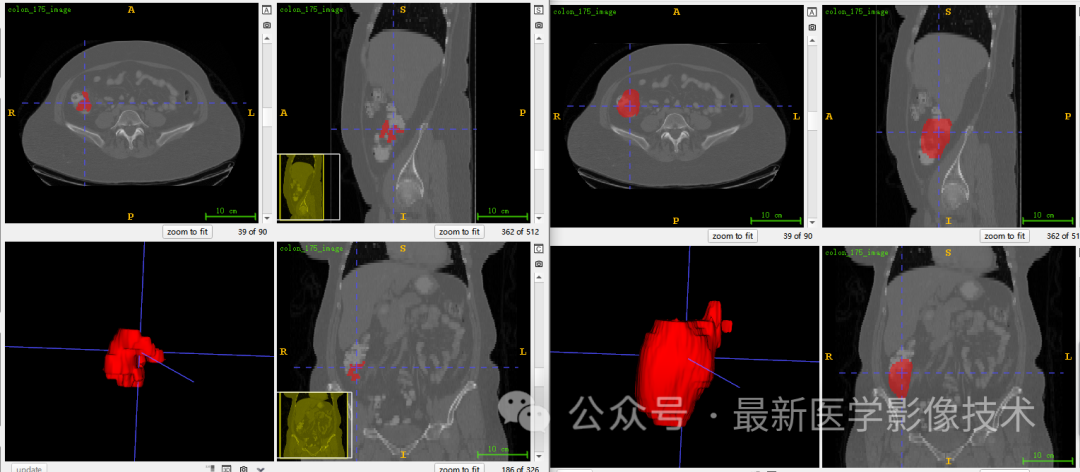

6、测试集分割结果